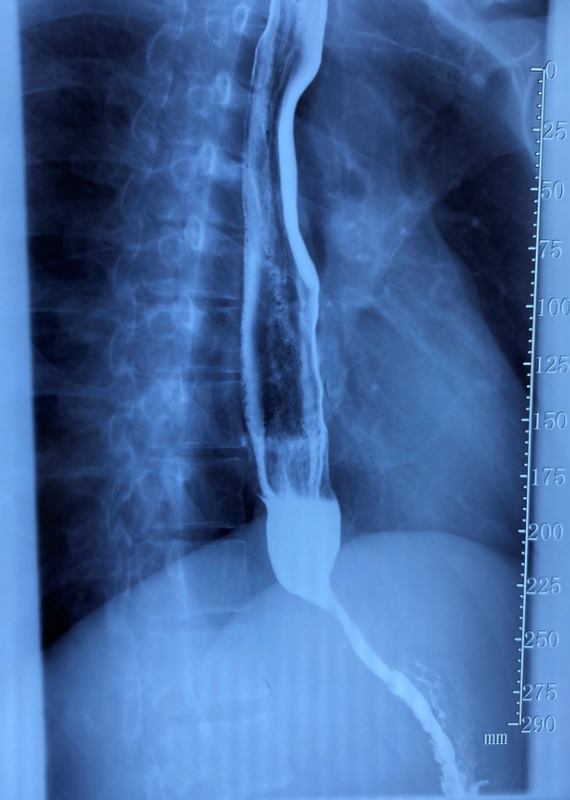

吞咽困難的原因可能是它——賁門失弛緩癥

賁門失弛緩癥是一種原發(fā)性食管神經(jīng)肌肉病變,主要表現(xiàn)為下食管括約肌松弛障礙、食管體部缺乏推進(jìn)性蠕動收縮的食管動力障礙性疾病。臨床主要表現(xiàn)為吞咽困難、反食、胸痛或胸部不適,并伴有燒心、體重減輕、呼吸道癥狀及精神心理的異常,嚴(yán)重影響患者的生活質(zhì)量。 診斷方法:食管鋇劑造影;內(nèi)鏡檢查;高分辨率食管測壓。 治療:一般治療;肉毒毒素治療;擴(kuò)張治療;手術(shù)。

什么是賁門失弛緩癥?賁門失馳緩癥,是一種由食管下括約肌張力增高和松弛障礙引起的,以進(jìn)食困難、反流、胸痛、反復(fù)肺部感染為主要表現(xiàn)的食管動力障礙性疾病,對患者生活質(zhì)量影響極大?;颊撸?男, 35歲, 在過去一年中,患者出現(xiàn)了反復(fù)進(jìn)食梗阻及胸痛,同時已經(jīng)影響到工作生活,隨后由我院食管內(nèi)鏡治療組接診?;颊叱霈F(xiàn)吞咽困難癥狀,可進(jìn)全流食,不能進(jìn)固體食物;有胸痛,偶有反流癥狀;胃鏡檢查提示食道有擴(kuò)張,齒狀線清晰,45cm過賁門賁門明顯狹窄,胃鏡勉強(qiáng)通過。食管造影提示賁門失弛緩癥。入院前患者在外院未行進(jìn)一步治療,同時不能進(jìn)食固體食物,遂來我院診治。造影圖片--鳥嘴征術(shù)前胃鏡圖片術(shù)前食管功能檢測:2020.9本院食管功能:食管下高壓帶靜息壓31.8mmHg,長度3.4cm,綜合松弛壓12mmHg,濕性吞咽時食管體90%表現(xiàn)為無效收縮蠕動,其中40%為蠕動;CD-LES基本位置重置;食管體長度23-24CM左右,食管腔內(nèi)24-Ph檢測,DeMeester得分2.17(<14.72)檢查結(jié)論食管動力學(xué)測定,食管下高壓帶靜息壓、長度及綜合松弛壓正常,濕性吞咽時食管體90%表現(xiàn)為無效收縮蠕動,(DCI為38mmHg.s.cm), 食管動力表現(xiàn)為“食管蠕動障礙”結(jié)合臨床其他檢查,DeMeester得分正常(酸暴露總時間占0.1%)?;颊吣壳搬槍S門失弛緩癥的治療目的在于降低LES壓力,使食管下端松弛,以解除括約肌痙攣、緩解癥狀。治療方式主要包括藥物治療、內(nèi)鏡治療及手術(shù)治療三方面。內(nèi)鏡治療措施主要有擴(kuò)張術(shù)、內(nèi)鏡下肉毒素注射、自膨脹型支架置入術(shù)以及經(jīng)口內(nèi)鏡下肌切開術(shù)(POEM);手術(shù)治療方式為外科Heller肌切開術(shù)。我們最后決定為患者進(jìn)行POEM手術(shù)治療。POEM,經(jīng)口內(nèi)鏡下肌切開術(shù)是一種通過隧道內(nèi)鏡技術(shù)進(jìn)行肌切開的內(nèi)鏡微創(chuàng)技術(shù)。2008年被首次應(yīng)用于賁門失弛緩癥臨床治療,取得了較好療效,目前已逐漸成為治療賁門失弛緩癥的首選治療方法。消化道的管壁一共分四層,黏膜層、黏膜下層、肌層和漿膜層。其中,黏膜下層最疏松,注入生理鹽水以后,可以成為內(nèi)鏡操作的又一空間,即內(nèi)鏡“第三空間”。內(nèi)鏡可以深入黏膜下層,在里面“打隧道”,直接到達(dá)病變部位,進(jìn)行相應(yīng)治療,POEM術(shù)就是運(yùn)用了這一原理。對患者而言,最大的好處是不開刀,只須在人體的自然腔道——食管粘膜上開一個小創(chuàng)口,利用粘膜下隧道技術(shù),切斷食管下段和賁門括約肌,免去了開胸破腹之痛。這種手術(shù)是在食道管壁的黏膜層和肌肉層之間進(jìn)行。手術(shù)步驟黏膜下注射;隧道入口;內(nèi)鏡“鉆入”粘膜下隧道黏膜下建立長隧道;沿黏膜下潛行分離至賁門下2cm食管肌層切開;切斷食管下段和賁門括約??;閉合隧道入口操作步驟:內(nèi)鏡見食管中下段管腔擴(kuò)張,齒狀線清晰,45cm過賁門賁門明顯狹窄,胃鏡勉強(qiáng)通過。在距離門齒33cm食管黏膜下注射生理鹽水,+腎上腺+靛胭脂后,黏膜抬舉良好,沿黏膜下潛行分離至賁門下2cm,建立黏膜下層隧道,應(yīng)用海博刀自上自下完全切斷肌束,創(chuàng)面止血,并用止血夾關(guān)閉隧道,術(shù)后賁門口明顯擴(kuò)大,胃鏡無阻力通過。術(shù)后復(fù)診:患者術(shù)后出現(xiàn)右側(cè)胸腔少量積液, 沒有發(fā)熱及臨床癥狀, 考慮食管肌層全層切開后的反應(yīng),三天后出院, 主述進(jìn)食明顯改善。 術(shù)后6月食管鏡:賁門略松弛,內(nèi)鏡通過無阻力。術(shù)后食管功能測試食管下高壓帶靜息壓18.2mmHg,長度3.6cm,綜合松弛壓6.7mmHg;濕性吞咽時食管體多表現(xiàn)為無效收縮蠕動,其中50%失蠕動;CD-Les基本位置相對重疊;食管體長度23-24cm左右。食管腔內(nèi)24h-PH監(jiān)測,DeMeester得分0.2食管腔內(nèi)24h-阻抗監(jiān)測:仰臥時混合反流為3.4結(jié)果:食管下靜息壓、長度及綜合松弛壓正常。患者經(jīng)過手術(shù)治療后,患者癥狀明顯改善體重增加,預(yù)后良好。第二例患者,女,60歲,8年前在外院行POEM手術(shù),目前又出現(xiàn)進(jìn)食梗阻及食管功能異常, 建議患者行腹腔鏡手術(shù)或再次POEM,患者堅決希望再次內(nèi)鏡下手術(shù),手術(shù)方式與初治患者一樣, 但考慮既往一般使用6點(diǎn)方向的隧道, 本次使用12點(diǎn)方向建立隧道。手術(shù)圖片省略。 胸科醫(yī)院張杰主任醫(yī)師、蘇瑜琛主治醫(yī)師及沈馮佳進(jìn)修醫(yī)師供稿。

患者男性, 王某,31歲,發(fā)作性進(jìn)行性吞咽困難4年,加重伴咳嗽5月,4年無明顯誘因出現(xiàn)吞咽困難,偶有嘔吐,5月前癥狀加重,每餐需飲水送服,偶有飲水困難,同時伴有反酸、咳嗽。當(dāng)?shù)蒯t(yī)院行食管造影提示:造影劑通過賁門受阻,賁門開放欠佳,以上食管擴(kuò)張,下端呈“鳥嘴樣”狹窄:低張后見賁門較前開放,造影劑下行受阻程度、食管擴(kuò)張程度較前減輕;診斷:賁門失弛緩癥。近日,王某經(jīng)人經(jīng)人介紹來到西安市第七醫(yī)院(交大附屬胸科醫(yī)院)消化中心就診,中心主任盧王詳細(xì)詢問了患者的病史,明確診斷后經(jīng)和患者及家屬充分溝通,盧王主任決定為患者實施經(jīng)口內(nèi)鏡食管下肌切開(POEM)手術(shù)。 術(shù)后第二天開始進(jìn)流質(zhì)軟食,第三天進(jìn)半流食,之后逐漸過度為普通飲食,吞咽困難得到明顯改善,未出現(xiàn)嚴(yán)重并發(fā)癥,術(shù)后1周順利出院。 科普時間什么是賁門失弛緩癥賁門失弛緩癥是一種食管神經(jīng)肌肉功能障礙性疾病,主要由食下端括約肌(LES)無法松弛及食管體部失去蠕動等造成。臨床主要表現(xiàn)為吞咽困難、食管反流及胸痛癥狀。內(nèi)鏡下可發(fā)現(xiàn)食管內(nèi)潴留較多食物及唾液,賁門緊閉;而鋇餐呈特征性“鳥嘴征”。 什么是POEM手術(shù)“經(jīng)口內(nèi)鏡下食管括約肌切開術(shù)”(peroral endoscopicmyotomy,POEM)。在我國目前已經(jīng)成為治療賁門失弛緩癥的首選,病人無需開胸手術(shù),全部手術(shù)過程均在無痛狀態(tài)下通過胃鏡操作,在患者食管黏膜下層建立一個“隧道”,然后內(nèi)鏡直視下自上而下、由淺入深縱行切開環(huán)形肌束,可使患者食管下段高壓得到即時解除,然后用金屬夾子將之前建立的“隧道”封閉。手術(shù)時間短、創(chuàng)傷小、安全性高,患者第二天即可進(jìn)食。 POEM手術(shù)的優(yōu)勢以往:賁門失弛緩癥的治療包括口服藥物、內(nèi)鏡下注射藥物、球囊擴(kuò)張和支架治療等方法,但不能最終解除食管下端括約肌梗阻,療效不肯定,復(fù)發(fā)率較高;外科手術(shù)切開食管下端括約肌療效確切,但手術(shù)創(chuàng)傷大,恢復(fù)慢,住院時間長,并且容易發(fā)生食管瘺、縱膈感染等并發(fā)癥,給患者帶來痛苦。 現(xiàn)在:POEM微創(chuàng)手術(shù)的開展,不僅大大克服了傳統(tǒng)治療的療效不確定性,而且恢復(fù)快、療效可靠、安全性高,充分體現(xiàn)了微創(chuàng)治療的優(yōu)越性。 NEWS經(jīng)口內(nèi)鏡食管下肌切開術(shù)(POEM)手術(shù)雖然作為一種國際最前沿的新型有效微創(chuàng)、安全性高、并發(fā)癥少治療賁門失弛緩癥的方法,但對術(shù)者的要求極高,需要具有嫻熟的內(nèi)鏡操作技術(shù)和現(xiàn)場復(fù)雜情況的操控能力,目前較少醫(yī)院開展。 2020年開科以來,西安市第七醫(yī)院(交大胸科醫(yī)院)消化中心多次運(yùn)用最新的內(nèi)鏡微創(chuàng)技術(shù),為賁門失遲緩患者成功進(jìn)行了經(jīng)口內(nèi)鏡下肌切開術(shù)(POEM),并憑借POEM手術(shù)視頻在2021年獲得了全國第五屆愛爾博手術(shù)視頻大賽菁英獎,同時,七院消化中心積極開展了多項內(nèi)鏡下診療技術(shù),如內(nèi)鏡粘膜下剝離術(shù)(ESD)、內(nèi)鏡粘膜下切除術(shù)(EMR),內(nèi)鏡下逆行胰膽管造影術(shù)(ERCP)、超聲內(nèi)鏡(小探頭)、內(nèi)鏡下食管胃底靜脈曲張精準(zhǔn)斷流術(shù)(ESVD)、透明帽輔助內(nèi)痔硬化術(shù)(CASE)等,標(biāo)志著西安市第七醫(yī)院(交大胸科醫(yī)院)消化中心診療技術(shù)已達(dá)到國內(nèi)先進(jìn)水平。 西安市第七醫(yī)院(胸科醫(yī)院)乘車路線路線一:地鐵四號線(航天新城方向)航天大道站(A口)出站后乘坐259路公交車五雁路下車 路線二:地鐵四號線(航天新城方向)金滹沱站(B口)出站后乘坐113路公交車杜陵西路西段站下車 西安市胸科醫(yī)院消化內(nèi)科作為我院消化疾病的診療和研究中心,具有國內(nèi)高水平的消化臨床診療水平。為患者提供最優(yōu)質(zhì)的服務(wù)和最先進(jìn)的醫(yī)療技術(shù),是我們工作的永恒宗旨。 科室地址:西安市長安區(qū)航天大道東段西安市胸科醫(yī)院門診樓二層西側(cè)消化內(nèi)鏡中心

轉(zhuǎn)自:中華消化內(nèi)鏡雜志, 2020,37(04) 李偉灃, 黃東良, 龔偉, 等疾病概述賁門失弛緩癥又稱賁門痙攣、巨食管,是由于食管神經(jīng)肌肉功能障礙所致的疾病,其主要特征是食管缺乏蠕動,食管下括約肌(LES)高壓以及對吞咽動作的松弛反應(yīng)減弱。臨床表現(xiàn)為咽下困難、食物反流和下端胸骨后不適,以及因食物反流誤吸入氣管所致咳嗽、肺部感染等癥狀。該病治療不及時,有發(fā)生食管癌的潛在危險。AC造影圖片--鳥嘴征賁門失弛緩癥的治療目的在于降低LES壓力,使食管下端松弛,以解除括約肌痙攣、緩解癥狀。治療方式主要包括藥物治療、內(nèi)鏡治療及手術(shù)治療三方面。內(nèi)鏡治療措施主要有賁門氣囊擴(kuò)張術(shù)、內(nèi)鏡下肉毒素注射、自膨脹型支架置入術(shù)以及經(jīng)口內(nèi)鏡下肌切開術(shù)(POEM);手術(shù)治療方式為外科Heller肌切開術(shù)。經(jīng)口內(nèi)鏡下肌切開術(shù)(POEM)是一種通過隧道內(nèi)鏡進(jìn)行肌切開的微創(chuàng)新技術(shù),2008年首次用于賁門失弛緩癥的治療。我國于2010年開始臨床使用POEM,經(jīng)過幾年的迅速發(fā)展,目前已成為開展該技術(shù)最多的國家。病例簡介一般情況及主訴 :28歲男性患者,因“吞咽困難2年余”入院。術(shù)前圖片:簡要病史 :2年前,患者出現(xiàn)吞咽困難癥狀,可進(jìn)全流食,不能進(jìn)固體食物;有胸痛,偶有反流癥狀;胃鏡檢查未見異常,食管造影提示賁門失弛緩癥。入院前3個月,患者在外院接受球囊擴(kuò)張術(shù),術(shù)后有好轉(zhuǎn),可進(jìn)半流食,仍不能進(jìn)食固體食物,遂來我院診治。手術(shù)步驟經(jīng)口內(nèi)鏡下肌切開術(shù)操作圖 (非本病例)1A:術(shù)前可見食管扭曲擴(kuò)張;1B:黏膜下注射;1C:隧道入口;1D:黏膜下隧道;1E:環(huán)形肌切開;1F:閉合隧道入口1. 黏膜下注射常規(guī)插入內(nèi)鏡,測量賁門距門齒距離,觀察賁門情況。退鏡至賁門口上方10 cm處,用注射器抽取配制好的生理鹽水250 ml、靛胭脂1 ml、腎上腺素2 ml混合液,以注射針在食管前壁行黏膜下注射;2. 食管黏膜層切開充分隆起后應(yīng)用三角形末端手術(shù)刀(TT刀)、鉤刀(Hook刀)或海博刀(以下簡稱“刀”)縱行切開黏膜層2 cm顯露黏膜下層,沿縱行切口周邊行黏膜下剝離擴(kuò)大開口;3. 分離黏膜下層,建立黏膜下“隧道”用內(nèi)鏡前端透明帽撐開黏膜下層,用刀沿黏膜下層垂直于環(huán)形肌層自上而下分離,建立黏膜下“隧道”至賁門以下3~5 cm;4. 環(huán)形肌切開“隧道”建立后,在胃鏡直視下,用“刀”在“隧道”口下方1~2 cm,自上而下縱行切開環(huán)形肌至賁門下方2 cm,切開過程中由淺而深切斷所有環(huán)形肌,盡可能保留縱行肌,但在食管下端可行食管肌層全層切開。5. 退出“隧道”前再次觀察如果“隧道”內(nèi)有出血點(diǎn)或潛在出血點(diǎn),以電凝止血,金屬夾關(guān)閉黏膜層切口。6. 術(shù)后優(yōu)勢1. 該術(shù)式吸收了Heller肌切開的優(yōu)點(diǎn),完全切開食管下段環(huán)形肌層乃至全層切開,理論上具有與外科Heller肌切開相媲美的療效,目前國內(nèi)外文獻(xiàn)表明,短期隨訪效果明顯;2. 保留了內(nèi)鏡微創(chuàng)治療優(yōu)勢,創(chuàng)傷小,術(shù)后患者恢復(fù)快;3. 不損傷食管裂口以及食管與胃底間的銳角(His角),保留胃食管連接部正常解剖結(jié)構(gòu),術(shù)后反流性食管炎發(fā)生率低。相關(guān)注意事項一、術(shù)前準(zhǔn)備① 和患者充分溝通,向患者詳細(xì)介紹兩種治療方式的效果、并發(fā)癥及風(fēng)險,告知患者及家屬手術(shù)可能獲得的收益及風(fēng)險,如果患者同意手術(shù),簽署知情同意書;② 術(shù)前3天患者進(jìn)全流食,術(shù)前半小時應(yīng)用頭孢二代抗生素預(yù)防感染;③ 麻醉前,患者在清醒狀態(tài)下接受胃鏡檢查,清洗食管腔和胃內(nèi)食物殘渣及液體,避免誘導(dǎo)麻醉后誤吸導(dǎo)致窒息甚至吸入性肺炎。在清洗干凈后食管和胃之后,患者在左側(cè)臥位或仰臥位接受氣管插管全麻。二、術(shù)中注意事項① “隧道”應(yīng)選擇在前壁或右側(cè)壁,較容易通過賁門部,不破壞His角,防止反流;同時在剝離時,“隧道”處于高位,視野清晰。② 在建立“隧道”過程中,沿垂直環(huán)形肌方向剝離,保證“隧道”為直線。③ 剝離應(yīng)在直視下進(jìn)行,對小血管電凝止血,對大血管采用Coagrasper電凝預(yù)防出血。不慎切斷大血管出血時,沖洗后看清出血點(diǎn),用Coagrasper電凝止血。④ 術(shù)者及助手、麻醉師嚴(yán)密觀察患者生命體征、皮下氣腫等情況,術(shù)中縱隔皮下氣腫常無須處理,可自行吸收。對嚴(yán)重氣胸[氣道壓力超過20 mmHg,血氧飽和度(SpO2)<90%,行床旁胸片證實]者予以胸腔閉式引流,若氣道壓力恢復(fù),生命體征恢復(fù)正常,可酌情繼續(xù)手術(shù);若改善不明顯,則須終止手術(shù)。對術(shù)中氣腹明顯者,可用14G 穿刺針在右下腹麥?zhǔn)宵c(diǎn)穿刺放氣。由于CO2較空氣彌散和吸收快,建議使用CO2充氣,一旦發(fā)生氣胸、氣腹,CO2會很快被吸收,常無須進(jìn)一步處理。三、術(shù)后處理① 絕對臥床休息24小時,嚴(yán)密觀察生命體征的變化,注意有無皮下氣腫,有無腹痛、腹脹、嘔血、黑便等出血和穿孔的情況。② 手術(shù)當(dāng)天禁食,24小時后進(jìn)冷流質(zhì),3天后進(jìn)半流質(zhì),進(jìn)食后1~2小時不可平臥,1個月后方可進(jìn)普食。③ 注意體溫的變化,給予靜脈輸液營養(yǎng),抗生素抗感染,質(zhì)子泵抑制劑制酸、止血等治療。④ 術(shù)后1個月、3個月、6個月復(fù)查胃鏡、食管造影、食管測壓。